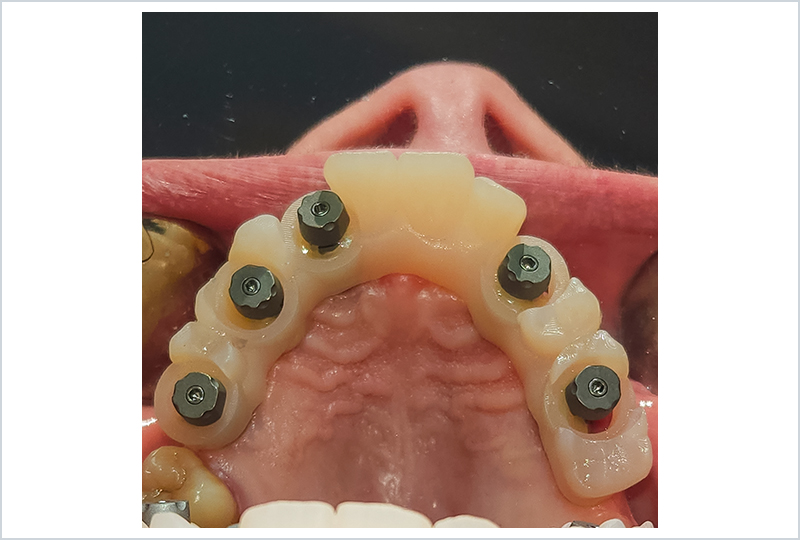

ODT Giovanni Rossi: Il paziente ci è ben noto, è una nostra conoscenza recente ma importante. Con lui abbiamo intrapreso un percorso di pianificazione chirurgica, riabilitato in carico immediato con una protesi stampata e caratterizzata nei toni rosa in composito.

Dopo alcuni mesi abbiamo finalmente raggiunto la completa maturazione dei tessuti e la perfetta integrazione degli impianti. Il paziente è soddisfatto del suo provvisorio, tanto da chiedere più volte: "Perché non lasciamo questa protesi? È perfetta!" (Figure 1, 2).

Fig. 1

protesi provvisoria a carico immediato dopo l'integrazione degli impianti